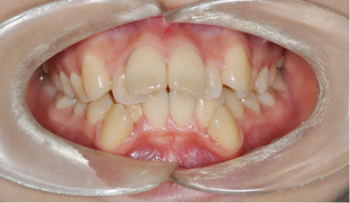

성장기 아동의 교정 치료

자료 채득

X-ray, 구강 내ㆍ외 카메라 사진, 치아 모형, 턱관절 및 치주 상태,